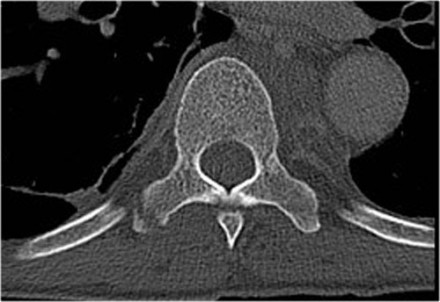

Continue with the axial images.

On the axial images we see:

- Transverse process fractures

- A rib fracture

These are typical findings in translation-rotation fractures.

So we should call this a translation fracture with anterior displacement.